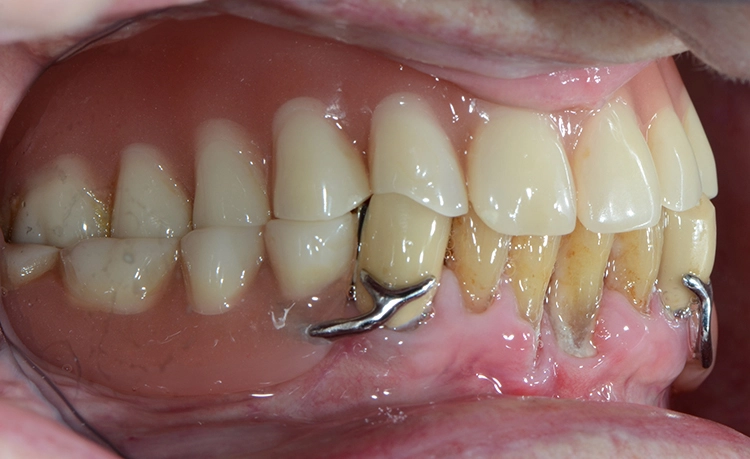

Bei den meisten alltäglichen Tätigkeiten wie Körperpflege und Kochen gaben die 100-Jährigen an, Hilfe zu benötigen. Obwohl offensichtliche Defizite in der häuslichen Mundhygiene vorlagen, wie generalisiert harte und weiche Beläge, schlecht gereinigter herausnehmbarer Zahnersatz, Druckstellen usw., gaben nur 7 (12,7%) der 100-Jährigen an, hierbei Hilfe zu benötigen. Die Abbildungen 1 bis 3 zeigen beispielhaft die klinische intraorale Situation von 3 100-Jährigen, die an der Untersuchung teilgenommen haben.